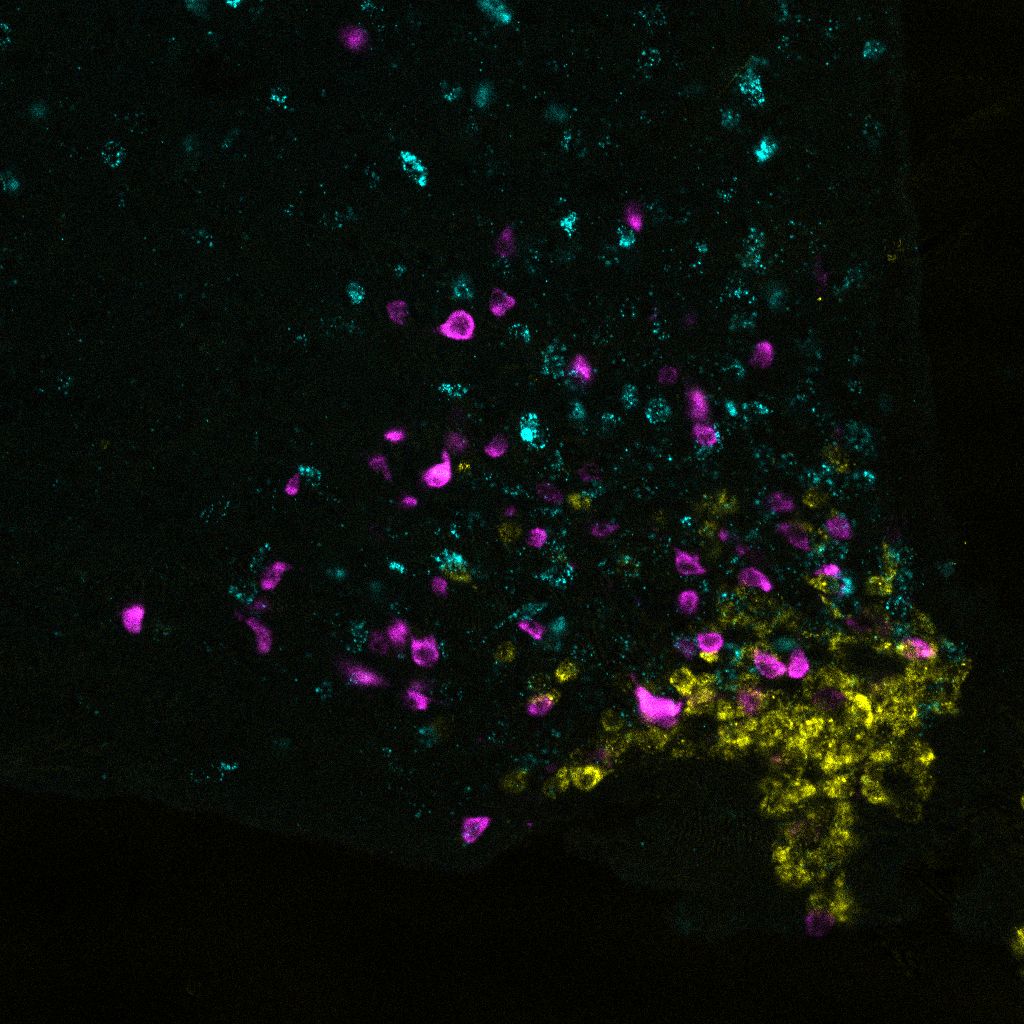

So entdeckte er zum Beispiel die zentrale Rolle der nur rund 3.000 sogenannten AgRP-Zellen im Hypothalamus, einer Gehirnregion, die an den meisten hormonell gesteuerten Prozessen beteiligt ist. Mit neuartigen Techniken konnte er zeigen, dass diese kleine Gruppe von Zellen bestimmt, wie viel wir essen und wie viel Glukose die Leber aus unseren Fettreserven freisetzt. Diese Zellen steuern auch, wie empfindlich unsere Körperzellen auf Insulin reagieren. Zusätzlich entdeckte er, dass die AgRP-Zellen bei Fettleibigkeit nicht mehr auf Insulin reagieren. Aufgrund dieser sogenannten Insulin-Resistenz können sie ihre Aufgaben nicht mehr erfüllen. Brünings umfangreiche Erkenntnisse über diese Zellen haben neue Möglichkeiten eröffnet, um Medikamente gegen Fettleibigkeit zu entwickeln, die durch Insulin-Resistenz entsteht.